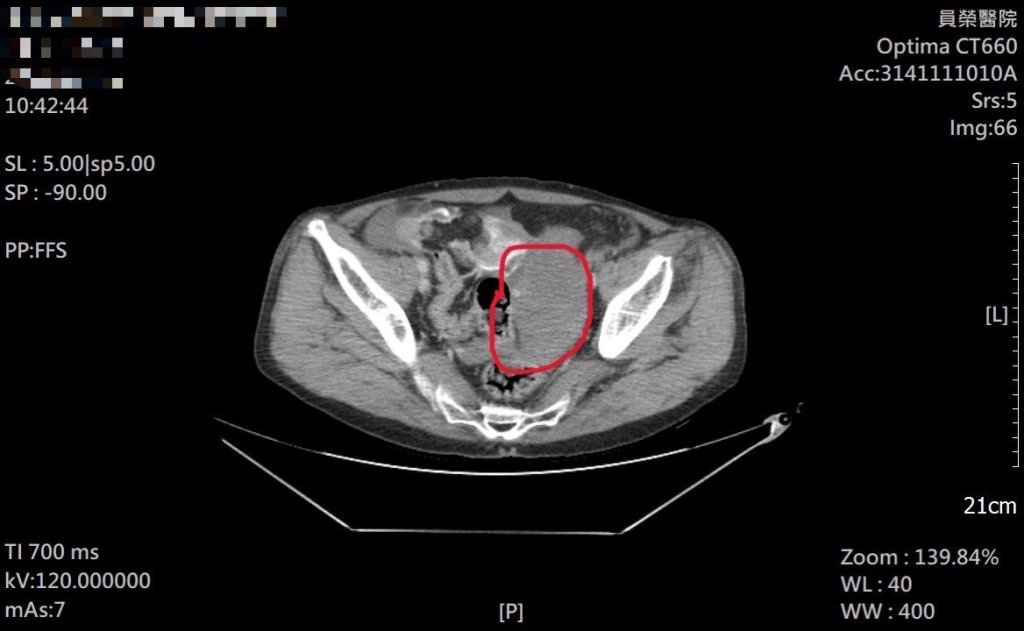

員榮急診團隊立即為患者施予止痛處置並安排抽血、X光與電腦斷層檢查。雖然四肢與頭部影像未見明顯骨折線,但CTA影像顯示疑似腸系膜出血,立即啟動緊急轉診。葉姓患者說,他在醫學中心接受二次手術,在加護病房住了十多天,一共住院長達四十多天,才撿回一命。